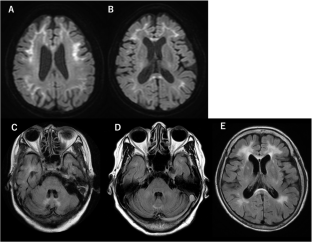

Neuronal intranuclear inclusion disease (NIID) is an autosomal dominant inherited neurodegenerative disease caused by NOTCH2NLC GGC repeat expansions. A high-intensity signal in the corticomedullary junction (CMJ) on magnetic resonance (MR) diffusion-weighted imaging (DWI) is a well-known characteristic of NIID. However, because of its diverse clinical symptoms and frequent presence of cerebral white matter hyperintensity (WMH) lesions on MRI, patients with NIID may be suspected of having other leukoencephalopathies. The aim of the present study was to identify patients with NOTCH2NLC GGC repeat expansions among those with undiagnosed leukoencephalopathies, recruited from NOTCH3-negative cerebral autosomal dominant arteriopathy with subcortical infarcts and leukoencephalopathy (CADASIL)-suspected and GFAP-negative Alexander disease (AxD)-suspected patients. Among 459 NOTCH3-negative CADASIL-suspected patients, 18 (3.9%) showed NOTCH2NLC GGC repeat expansions; however, among 40 GFAP-negative AxD-suspected patients, none exhibited such repeat expansions. On comparing 17 patients with GGC repeat expansions, whose clinical information was available, with 179 CADASIL probands previously reported by us, the former showed significantly higher frequencies of seizure (23.5 vs. 6.9%, respectively), WMH in the corpus callosum (92.9 vs. 9.2%, respectively), paravermis (21.4 vs. 2.7%, respectively), and middle cerebellar peduncle (21.4 vs. 3.4%, respectively), and DWI high-intensity signals in CMJ (61.5 vs. 1.4%, respectively). In conclusion, not only DWI high-intensity signals in CMJ, but also the WMH distribution, particularly a high frequency in the corpus callosum, and presence of seizures are useful for detecting NIID in patients with undiagnosed leukoencephalopathies.